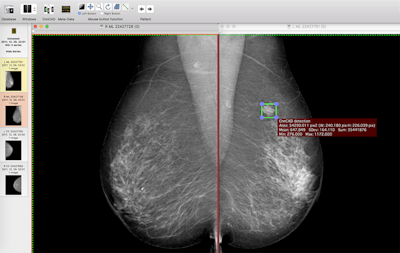

Craniocaudal view of a mammogram in left and right breast. The deep-learning-based CAD system identifies the area of the cancer (green box). All images courtesy of the Breast Research Group, INESC Porto in Portugal.

Mediolateral oblique view of a mammogram in left and right breast of the same woman. The deep-learning-based CAD system identifies the area of the cancer (green box).